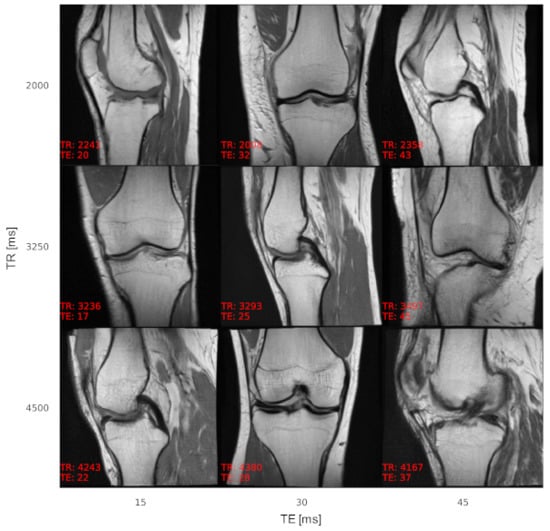

According to the experts, image quality impediments of synthetic MR images were mainly attributed to overly smooth tissue (muscles, fat tissue, and bones) compared to fibrous muscle tissue, granular texture in fat tissue, and fine structures in bones of real MR knee images. Additionally, due to the downsampling of several of the real images to a resolution of 256 × 256 pixels using bilinear interpolation to obtain identical image resolution, the image quality of the real images was described as inferior in certain cases, making it hard for the experts to classify. An example of acquisition parameter interpolation is shown in Figure 3, and additional examples of varying anatomy demonstrating the variability of the generated samples are shown in Figure 4. The effect of TE on the tissue contrast can be seen in signal changes of the muscle tissue (Figure 3). Varying TR results in signal differences in the fluid-cartilage contrast [42] and mainly affects contrast on T1-weighted images [43], which are not available within the dataset (see Section 5. Discussion). Therefore, the signal changes through varying TR are less prominent.

Figure 3. Acquisition parameter interpolation of TR and TE for a single latent vector. A single latent vector was reconstructed with different TR and TE values, showing the capability of the generator to synthesize MR images with adaptable image contrast. The axes describe the intended acquisition parameter values and the values at the bottom left of each image the output of the AC. The images are annotated (in red) with acquisition parameter values as determined by the AC, showing a low overall conditioning error. The contrast adapts properly within images along the axes; however, the anatomy also slightly changes, which is a sign of feature entanglement of the latent vector with the conditions.

Figure 4. Additional examples of synthetic MR images with varying TR and TE to show the variety of the generated image samples. The imaging orientation alternates between sagittal and coronal. The images are annotated (in red) with acquisition parameter values as determined by the AC, showing a low overall conditioning error.